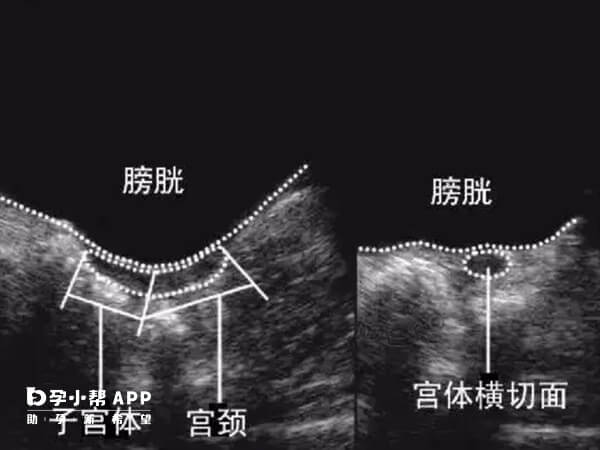

幼稚子宫属于发育畸形的一种,以目前的医疗技术并没有办法根治,幼稚子宫的处理办法要分为情况。